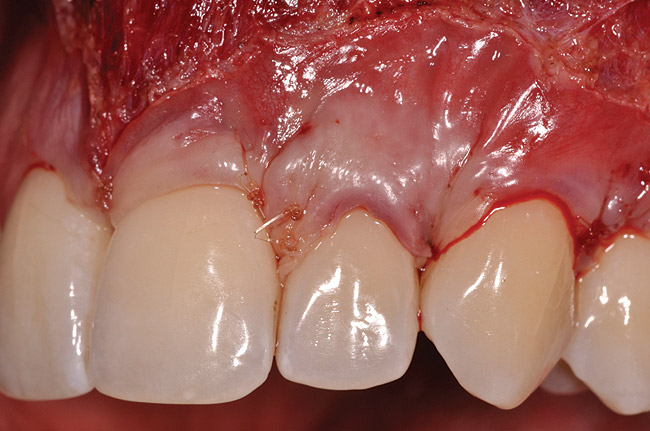

Closure was then accomplished by coronally repositioning the buccal flap and securing the flap using an interrupted sling suturing technique with 5.0 Monocryl™ (Ethicon, www.ethicon.com). The interrupted sling suture technique was started at the mesial aspect of each tooth in the area of the mucogingival junction, and passed interproximally to the distal aspect of the same tooth; the flap was then engaged in the mucogingival junction area, and the suture was passed back interproximally at the distal aspect palatally, then to the buccal from the mesial aspect of the tooth. The suture was then tied off at the mesial aspect. This closure technique was performed for each of the affected tooth sites (Figure 12 and Figure 13).

Once the flap was coronally repositioned and secured, a securing periosteal tac procedure was performed to prevent any micro movement superior to the mucogingival junction in the initial healing phase. A 4.0 chromic gut suture (Surgical Specialties Corp.) was used to engage the periosteum superior to the mucogingival junction and stabilize the tissues superior to the securing suture (Figure 12 and Figure 13). Multiple periosteal tac sutures may be necessary, depending on the size of the surgical field. Postoperatively, the periosteal tac sutures are routinely removed if not totally absorbed at 7 days; the flap sutures are removed at 2 to 3 weeks, and dermal-securing sutures are removed 1 month after surgery. The 1-year post-treatment clinical view shown in Figure 14 depicts the excellent soft-tissue result, band of attached keratinized tissue present, and excellent color match to the host gingival tissues.

Fig 12. Closure, lateral view, of case presented.

Figure 12

Fig 13. Closure, frontal view, of case presented.

Figure 13